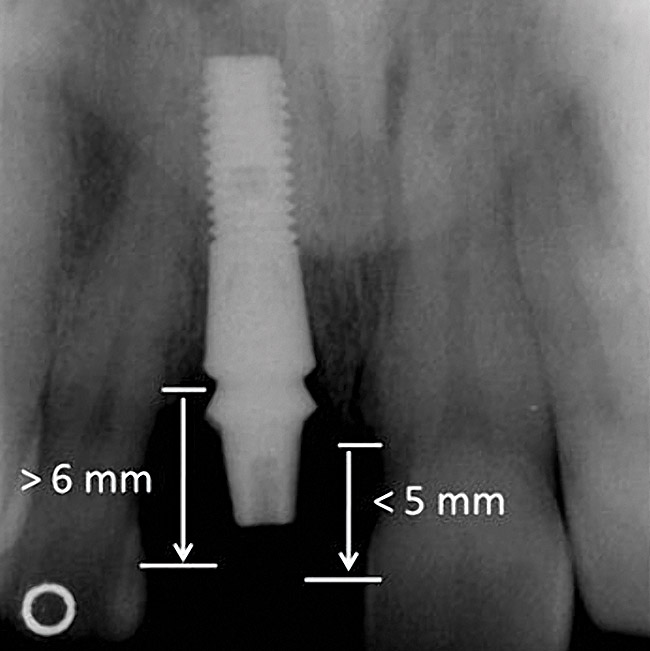

Figure 4  Characterization of the interproximal bone and tooth contacts: A periapical radiograph assists in measuring the distance from bone crest to the adjacent tooth contact points for missing tooth No. 8. The mesial bone crest to the adjacent tooth contact distance is < 5 mm, while the distal bone crest to adjacent tooth contact distance is > 6 mm (Fig 4). One-year following implant placement, conservation of these dimensions is revealed (Fig 5). The clinical photograph (Fig 6) of the lateral incisor adjacent to tooth No. 8 implant crown demonstrates that the absence of distal interproximal (papilla) fill related to the observed bone crest to contact distance exceeds 6 mm.

Figure 4

Figure 5  Characterization of the interproximal bone and tooth contacts: A periapical radiograph assists in measuring the distance from bone crest to the adjacent tooth contact points for missing tooth No. 8. The mesial bone crest to the adjacent tooth contact distance is < 5 mm, while the distal bone crest to adjacent tooth contact distance is > 6 mm (Fig 4). One-year following implant placement, conservation of these dimensions is revealed (Fig 5). The clinical photograph (Fig 6) of the lateral incisor adjacent to tooth No. 8 implant crown demonstrates that the absence of distal interproximal (papilla) fill related to the observed bone crest to contact distance exceeds 6 mm.

Figure 5